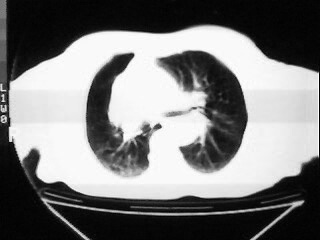

女,79,咳 嗽月余,无其它不适

1)两肺炎症。2)食管裂孔疝可能;建议行上消化道钡餐检查。

后纵隔内左心房至肝左叶后方椎体中线偏左巨大软组织包块,其壁均匀比较薄,其内可见宽气液平。

考虑食管裂孔疝。建议钡餐检查